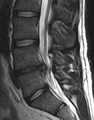

- التصوير بالرنين المغناطيسي هي الدراسة المعيارية الذهبية لتأكيد الاشتباه في انزلاق غضروفي. مع دقة تشخيصية تبلغ 97%، فهي الدراسة الأكثر حساسية لتصور الانزلاق الغضروفي بسبب قدرتها الكبيرة على تصور الأنسجة الرخوة. كما يتمتع التصوير بالرنين المغناطيسي بموثوقية أعلى بين المراقبين مقارنة بوسائل التصوير الأخرى. ويشير إلى انزلاق غضروفي عندما يظهر إشارة متزايدة مرجحة بـ T2 عند المنطقة الخلفية التي تغطي 10% من القرص. وقد أظهرت أمراض الانزلاق الغضروفي ارتباطًا بتغيرات النوع 1 من مقياس موديك. عند تقييم اعتلالات الجذور العصبية القطنية بعد الجراحة، فإن التوصية هي إجراء التصوير بالرنين المغناطيسي مع التباين ما لم يكن هناك موانع أخرى. يعد التصوير بالرنين المغناطيسي أكثر فعالية من التصوير المقطعي المحوسب في التمييز بين الأسباب الالتهابية أو الخبيثة للانزلاق الغضروفي. يُشار إليه في وقت مبكر نسبيًا في مسار التقييم (<8 أسابيع) عندما يظهر المريض مؤشرات نسبية مثل الألم الشديد والعجز الحركي العصبي ومتلازمة ذيل الفرس. التصوير الموتر الانتشاري هو نوع من تسلسل التصوير بالرنين المغناطيسي المستخدم للكشف عن التغيرات الدقيقة في جذر العصب. قد يكون مفيدًا في فهم التغييرات التي تحدث بعد أن يضغط القرص القطني المنفتق على جذر العصب، وقد يساعد في التمييز بين المرضى الذين يحتاجون إلى تدخل جراحي. في المرضى الذين لديهم شكوك عالية في اعتلال الجذور العصبية بسبب الانزلاق الغضروفي القطني، ومع ذلك فإن التصوير بالرنين المغناطيسي غامض أو سلبي، يوصى بدراسات التوصيل العصبي.[44] توفر الصور المرجحة الناتجة عن التصوير بالرنين المغناطيسي (T2) تصور واضح لمادة القرص البارز في القناة الشوكية.

التصوير بالرنين المغناطيسي للانزلاق الكبير (على اليمين) بين الفقرتين القطنيتين الرابعة والخامسة.

-

انزلاق شديد إلى حد ما بين الفقرتين القطنيتين الرابعة والخامسة.